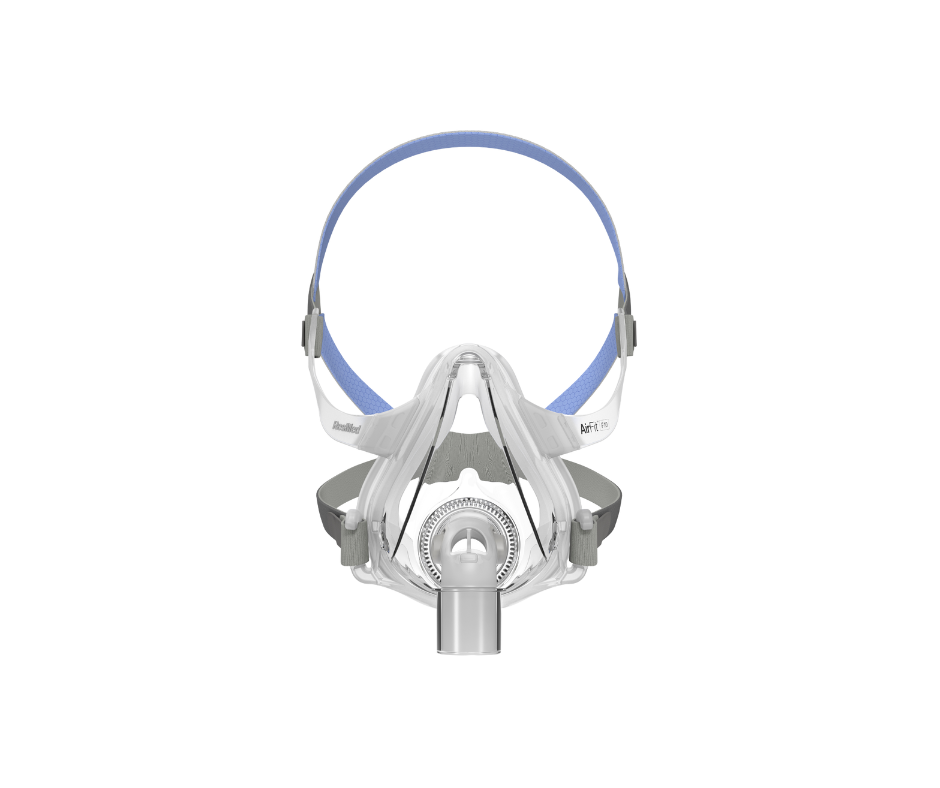

Terapia con CPAP

La mejor tecnología

Con más del 90% de aceptación de los pacientes, la tecnología de los equipos CPAP y VPAP es la ideal para el tratamiento de la Apnea Obstructiva del Sueño.